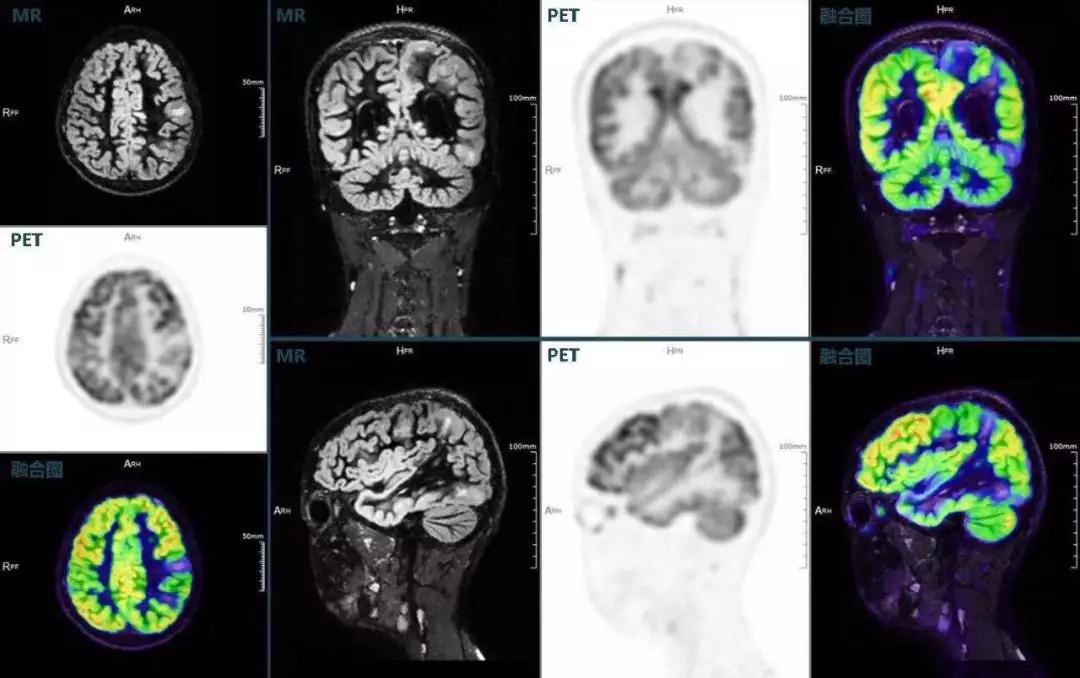

癲癇

不僅如此,聯(lián)影“時(shí)空一體”超清TOF PET/MR還搭載了大量可用于神經(jīng)疾病領(lǐng)域的高級(jí)應(yīng)用,如DIR(Double Inversion Recovery雙反轉(zhuǎn)恢復(fù))序列能夠清晰顯示大腦皮層的結(jié)構(gòu)成像,對(duì)于皮層腫脹,膠質(zhì)增生等癲癇的影像征象都能清楚呈現(xiàn);DTI(Diffusion Tensor Imaging彌散張量成像)高級(jí)應(yīng)用能夠顯示細(xì)小的神經(jīng)纖維束缺損,以更加定量的形式為醫(yī)生提供一個(gè)全新的診斷維度,輔助醫(yī)生精準(zhǔn)診斷。

(結(jié)節(jié)性硬化,MR DIR序列清晰顯示腦皮層病理改變,PET顯示了病灶區(qū)域FDG的低濃聚。PET/MR融合顯像同時(shí)提供了結(jié)構(gòu)異常改變和功能變化的信息。)